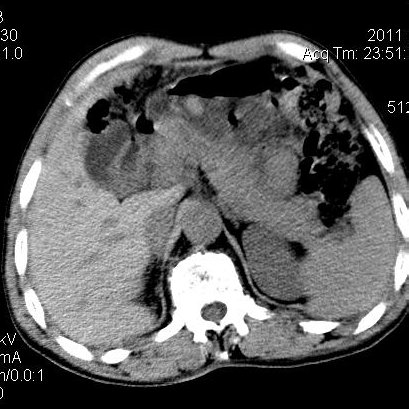

肝左叶发育异常

男性,55岁,骑摩托车摔倒后入院,自述右上腹疼痛

[backcolor=#FF0000]第一次诊断的时候也是这么肯定,可是床旁超声检查并没有发现明显异常,而且患者的一般症状都良好。还好临床只是保守治疗,没有立即手术,第二次复查的时候没有一点变化,又做了MRI检查,没有血肿,

这是一例肝左叶发育异常的,很个性吧~[/backcolor]